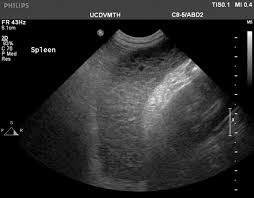

Whats New In Canine Lymphoma from cdn.sanity.io However, further studies are needed. However, localized forms of lymphoma can also occur in dogs, including lymphoma of the central Ensure that the dog is not put on aspirins since it will cause stomach ulcers. Eventually, the cancer will infiltrate an organ to such an extent that organ fails (often this is the bone marrow or the liver). This is the most common type of lymphoma that affects dogs. The prognosis for lymphoma varies, depending on various characteristics that can only be determined by specialized testing. Approximately 50% of dogs with lymphoma will respond to prednisone (a steroid) alone, but the remission times are only 2 to 4 months with prednisone alone. The life expectancy of a dog with lymphoma who goes without treatment is less than two months.